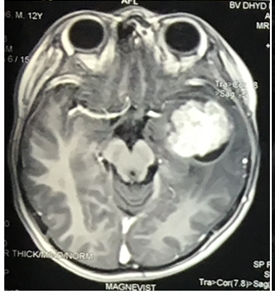

Dịch tễ học U não tiên phát ác tính vẫn là một thách thức trong y khoa. U nguyên bào thần kinh đệm (còn gọi là u tế bào thần kinh đệm độ IV, u sao bào độ IV) là u não tiên phát phổ biến và ác tính nhất. U nguyên bào thần kinh đệm là hình ảnh thu nhỏ của một nhóm u tế bào thần kinh đệm […]